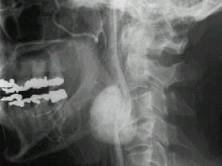

问题 50岁女性,颈部无痛性肿块,逐渐增大,听诊可闻及杂音,DSA检查如图所示,请选择最可能诊断 ( )

选项 A、颈动脉硬化 B、动静脉瘘 C、假性动脉瘤 D、颈动脉夹层 E、颈动脉体瘤

答案 E